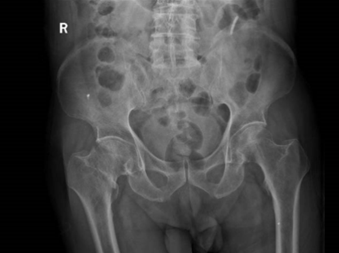

家住附近郑伯,已经95岁了,与老伴相依多年,日常生活完全自理,但郑伯不久前在家不慎跌倒后,一阵疼痛撕裂了岁月静好,他因右侧髋部剧痛无法站立,家人连忙将他送到我院急诊就诊,随后郑伯被创伤骨科刘兴漠主任医师团队收治入院。

经完善检查,确诊右侧股骨颈骨折,同时郑伯还有高血压病史,频发支气管哮喘,加上95岁高龄,如何治疗成了让人纠结的问题。